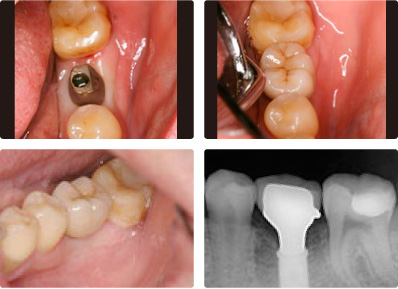

インプラント

治療前

治療後